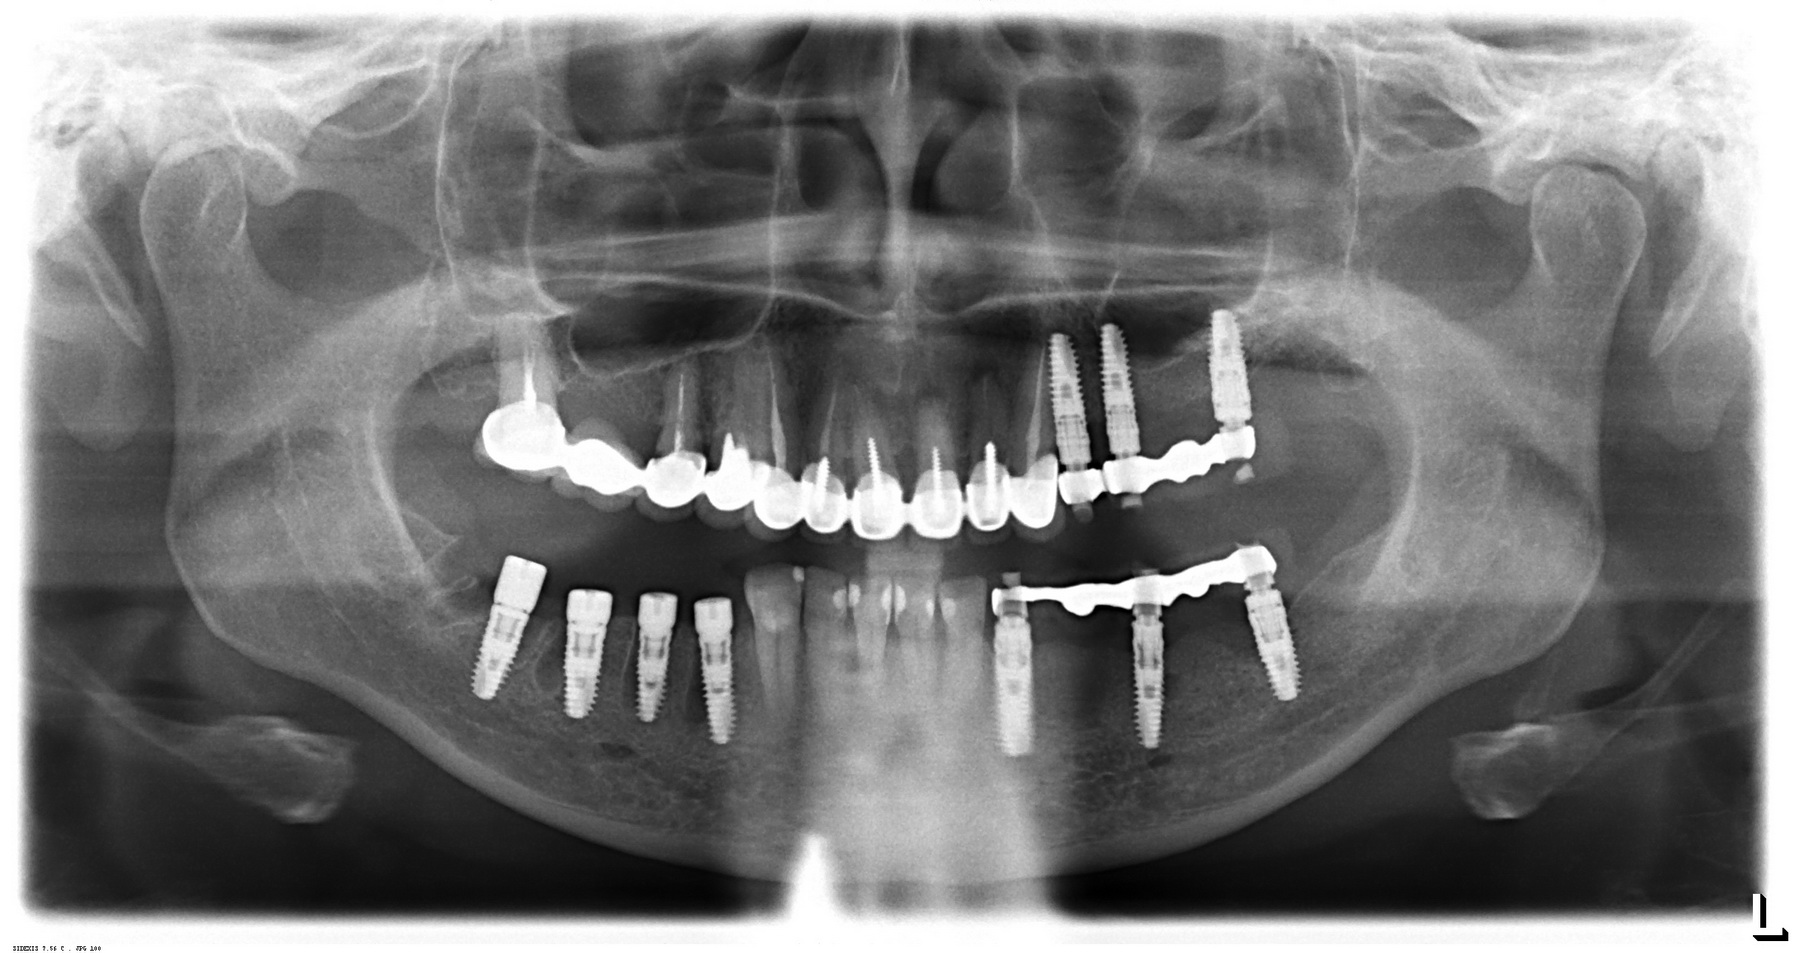

Вот пример. На этот раз, на снимках: пациентка, возрастом чуть больше сорока лет. После диагностики и необходимых исследований стало ясно, что необходимо хирургическое лечение во всех участках зубного ряда. В частности, удаление 13 зубов, включая ретинированный зуб мудрости, остеопластика на нижней челюсти и синуслифтинг, пластика слизистой и много чего еще.

У меня нет ипотеки и других долгов, поэтому я принимаю решение разбить весь объем хирургического лечения на четыре этапа — по одному в каждом из сегментов зубного ряда. И начинаю я… угадайте, с какого участка? Верно, с того, который уже не функционален из-за критического разрушения зубов — с левого нижнего:

Операция заняла всего 60 минут, послеоперационные явления были настолько незначительны, что пациентка чуть ли не через пару недель решилась на вторую операцию:

в ходе второго этапа было установлено три импланта в боковом сегменте верхней челюсти, удален ретинированный зуб мудрости, проведен синуслифтинг

Вторая операция заняла чуть больше времени (90 минут), поскольку потребовалось удаление ретинированного зуба мудрости и синуслифтинг. Послеоперационные явления более выраженные — отек держался в течение нескольких дней, болезненных ощущений почти не было.

третий этап работы: слева уже установлены временные протезы на имплантах, а справа удалены четыре зуба и одновременно установлены четыре импланта

Как вы думаете, сколько времени заняла третья хирургическая операция? 60 минут! Легко, быстро и комфортно. А главное — результативно!

Что в итоге получилось? Пока три этапа, по 60-90 минут каждый. Минимум времени операции, минимум травмы. Как результат — успешное комфортное лечение с высокой эффективностью и без больших единовременных затрат. Это всяко лучше, чем одна многочасовая дорогостоящая операция с тяжелым послеоперационным периодом и существенным дискомфортом. Вот вы бы что выбрали?